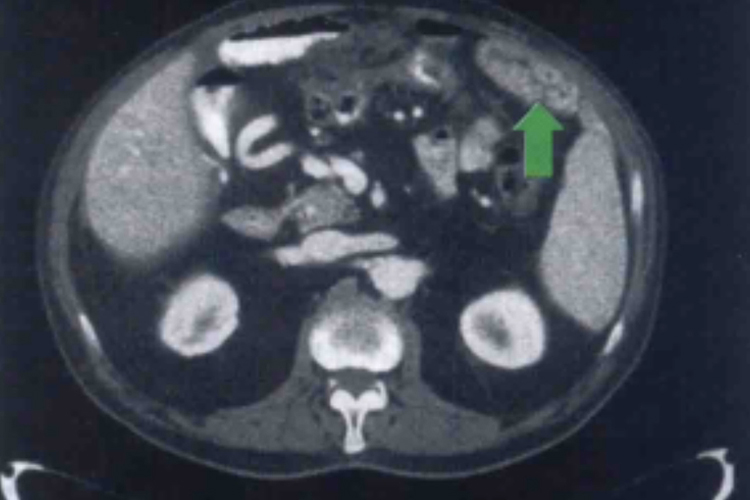

腹膜转移:伴有癌性腹水的腹膜转移是肿瘤转移超出腹腔范围的标志,这可通过在骨髓和血流中检测到微小转移灶明确诊断,胰腺癌腹膜转移可出现腹水,引起腹胀、腹痛等症状,进而导致患者营养不良,恶液质,影响患者生存时间。